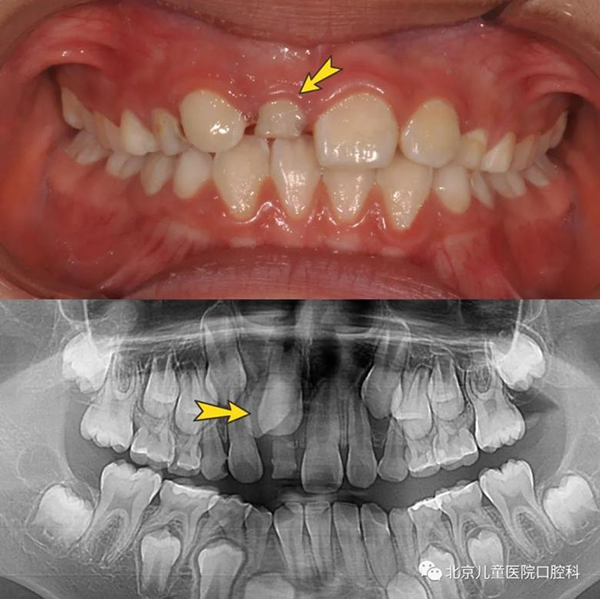

同时,在这个阶段孩子的乳牙逐渐替换为恒牙,有的时候周围的牙都替换了,却只有一颗牙迟迟不松动;有的时候乳牙脱落了很久,新牙还没有长出来;或者新牙长出来却是“扭着身子”的……这有可能是存在多生牙、融合牙、牙齿异位萌出、牙扭转等问题。

这些“隐性”问题可能无法自行发现,建议孩子6至7岁到口腔科就诊进行系统的口腔检查,需要时及时治疗,以免造成更严重的影响。

乳牙迟迟没有替换(上图),因为多生牙阻挡(下图)